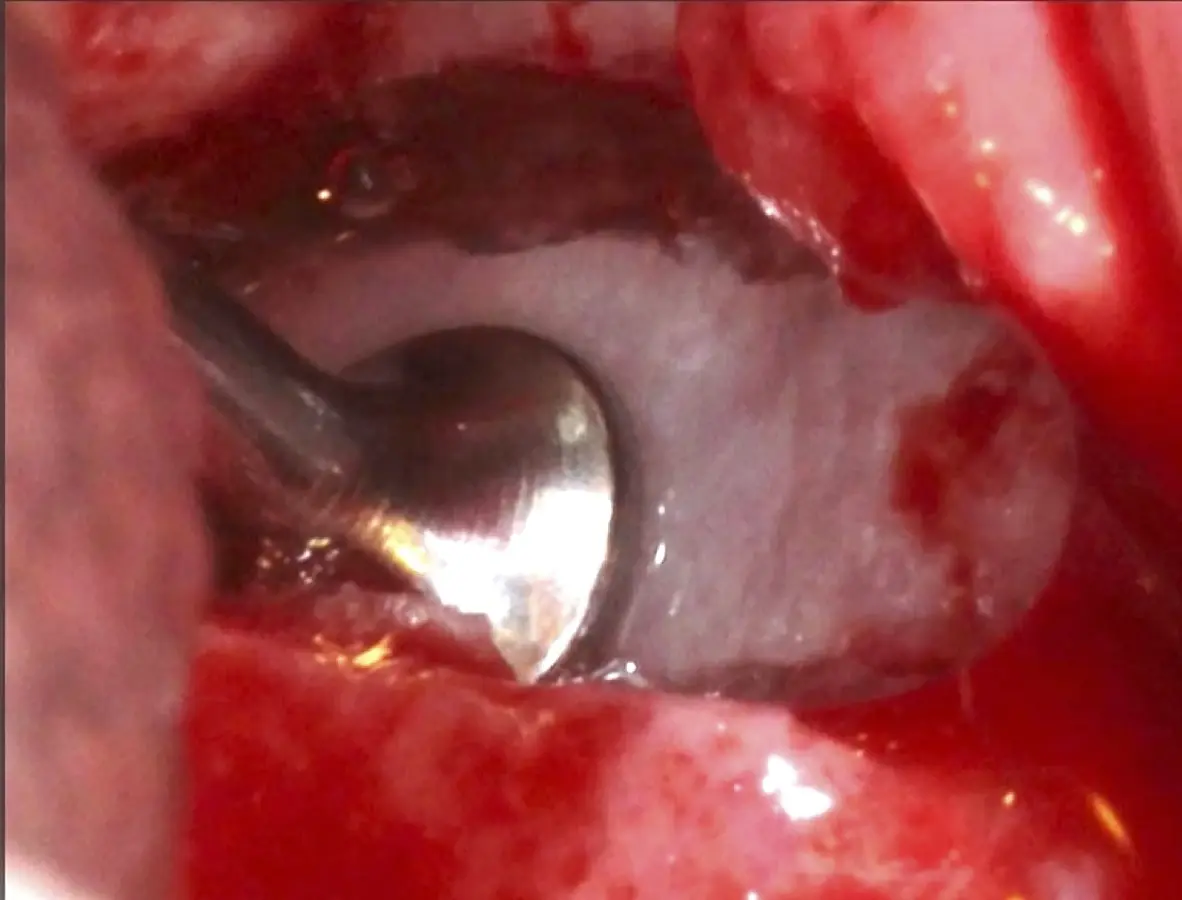

Se inicia la elevación de la membrana de Schneider con el inserto redondeado no cortante en forma de disco, empleando movimientos suaves. El levantamiento puede complementarse con elevadores convencionales, siguiendo la dirección mesiodistal. La fase de desprendimiento inicia con el piso y sigue hacia la pared mesial para terminar, y de ser necesario, hacia la pared posterior. Existen diversos insertos con angulaciones y longitudes para mayor accesibilidad16 (Figura 1).

Figura 1. Incisión y levantamiento de colgajo a espesor total.

Figura 16. Delimitación y osteotomía por desgaste de la ventana lateral con el inserto plano de punta diamantada (a). Retiro del bloque óseo (b).

Figura 17. Inicio del desprendimiento de la membrana de Schneider con el inserto de presión hidráulica.